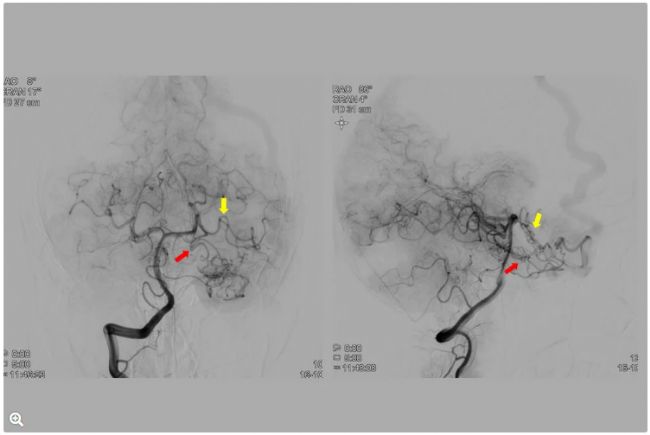

術前成像:AVM供血

圖3:術前DSA。AP投影,顯示AVM病灶大小為2.5 cm,部分由大腦中動脈經內部主干動脈的過早分支血管(藍色箭頭)和終末分支血管供血(紫色箭頭)。

圖4:側位投影。AVM也由大腦后動脈經顳下前動脈和顳下中動脈部分供血(分別為黃色和紅色箭頭)。